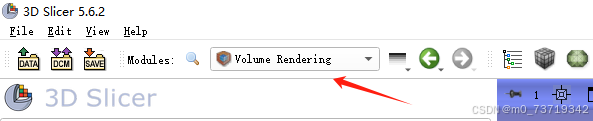

2.重建三维图像

点击该按钮选择Volume Rendering